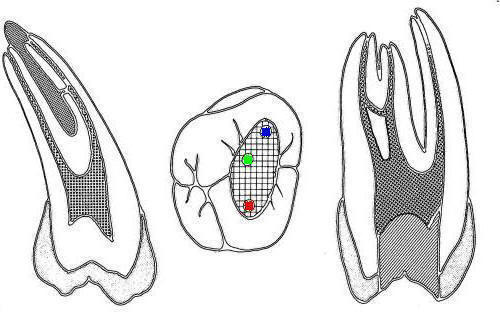

Molares inferiores |

1º molar inferior (1,2,23,27)

En azul conducto mesio-vetibular

-

En verde conducto mesio-lingual

En rojo conducto distal

En amarillo un cuarto conducto,

si el conducto distal se encuentra desplazado hacia lingual,

existe una alta posibilidad de encontrar un cuarto conducto

|

| 2º molar inferior (1,2,23,27)

Similar al primer molar inferior pero menos voluminoso, en la

raíz mesial siempre encontrará dos conductos y en la raíz distal

puede encontrar uno ó dos conductos.

En azul conducto mesiovetibular

En verde conducto mesiolingual